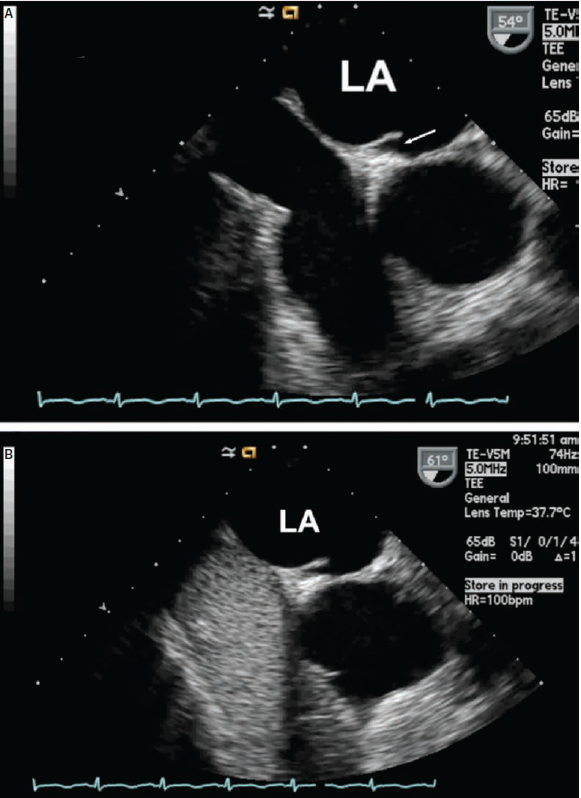

Transesophageal echocardiography is the main imaging modality to recognize the LASP. The presence of a LASP is typically evaluated in the bi-caval view (with transducer in the mid-esophageal position and angled 90-110 degrees) and in the short-axis view (with transducer in the mid-esophageal position and angled 25-45 degrees). Panels A and B of Figure 4 show a typical short-axis image of a left atrial septal pouch. A prerequisite to the recognition of the septal pouch is the demonstration of no connection between the left and right atria, ie, coexistence of the PFO and LASP cannot be observed, and the two are mutually exclusive. Shown in Figure 4 B is an example of bubble opacification of the right atrium with a Valsalva maneuver with no bubbles seen in the left atrium.